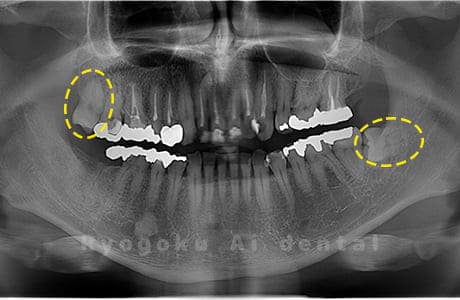

Case02

- 原因

- 下顎の水平埋伏智歯

- 治療内容

- 下顎の水平埋伏智歯を抜歯

<リスク・副作用>

手術後は痛み、腫れ、痺れなどの副作用が生じる場合があります。